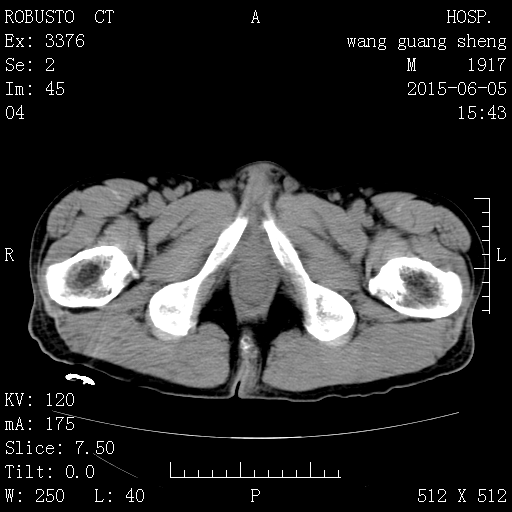

CT50574:右下腹部包块,请各位老师看看。

老年男性,无明显不适,一月前偶然触摸到右下腹部一包块

结肠占位

ca可能性大

倾向于:病变范围广,淋巴瘤可能

结肠癌可能性大,建议行结肠镜检查进一步确诊。

病变范围较广泛,肠管柔软未见梗阻征象,考虑淋巴瘤可能性大。

考虑结肠间质瘤,建议强化或肠镜检查